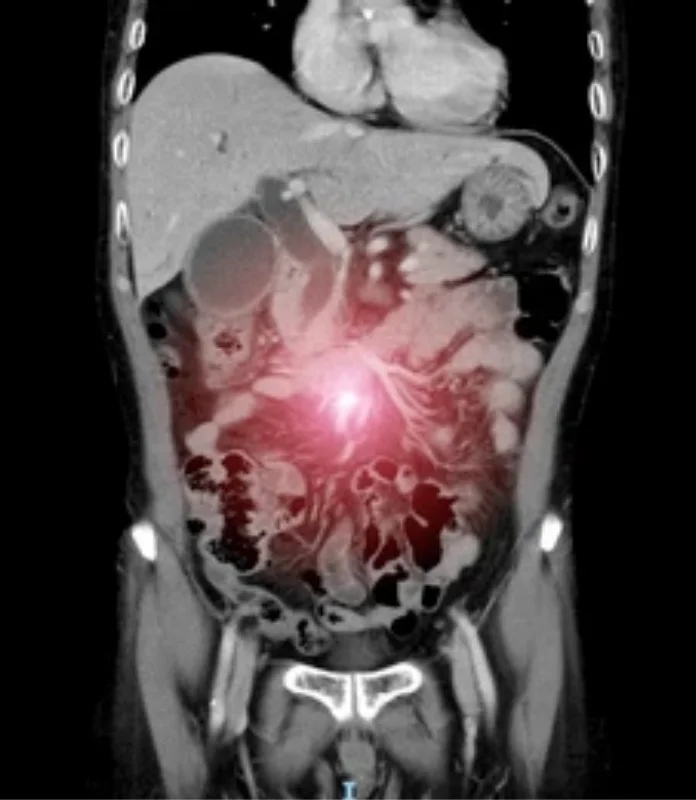

Minimally Invasive (Laparoscopic & Robotic) Oncologic Procedures in Ahmedabad

Advanced Cancer Surgery with Precision, Safety, and Faster Recovery

Minimally Invasive Cancer Surgery with Advanced Precision

Laparoscopic and robotic oncologic procedures designed to treat cancer effectively while minimizing surgical trauma.

Minimally invasive oncologic surgery uses advanced laparoscopic and robotic techniques to remove cancer through small incisions, reducing pain, recovery time, and surgical stress on the body. When performed by a trained surgical oncologist, these procedures offer excellent cancer control with added patient comfort. Under the care of Dr. Anuj Suketu, minimally invasive cancer surgery is offered for selected patients across gastrointestinal, gynecologic, urologic, and HPB cancers. Each case is carefully evaluated to ensure that cancer safety is never compromised while delivering the benefits of modern surgical technology.